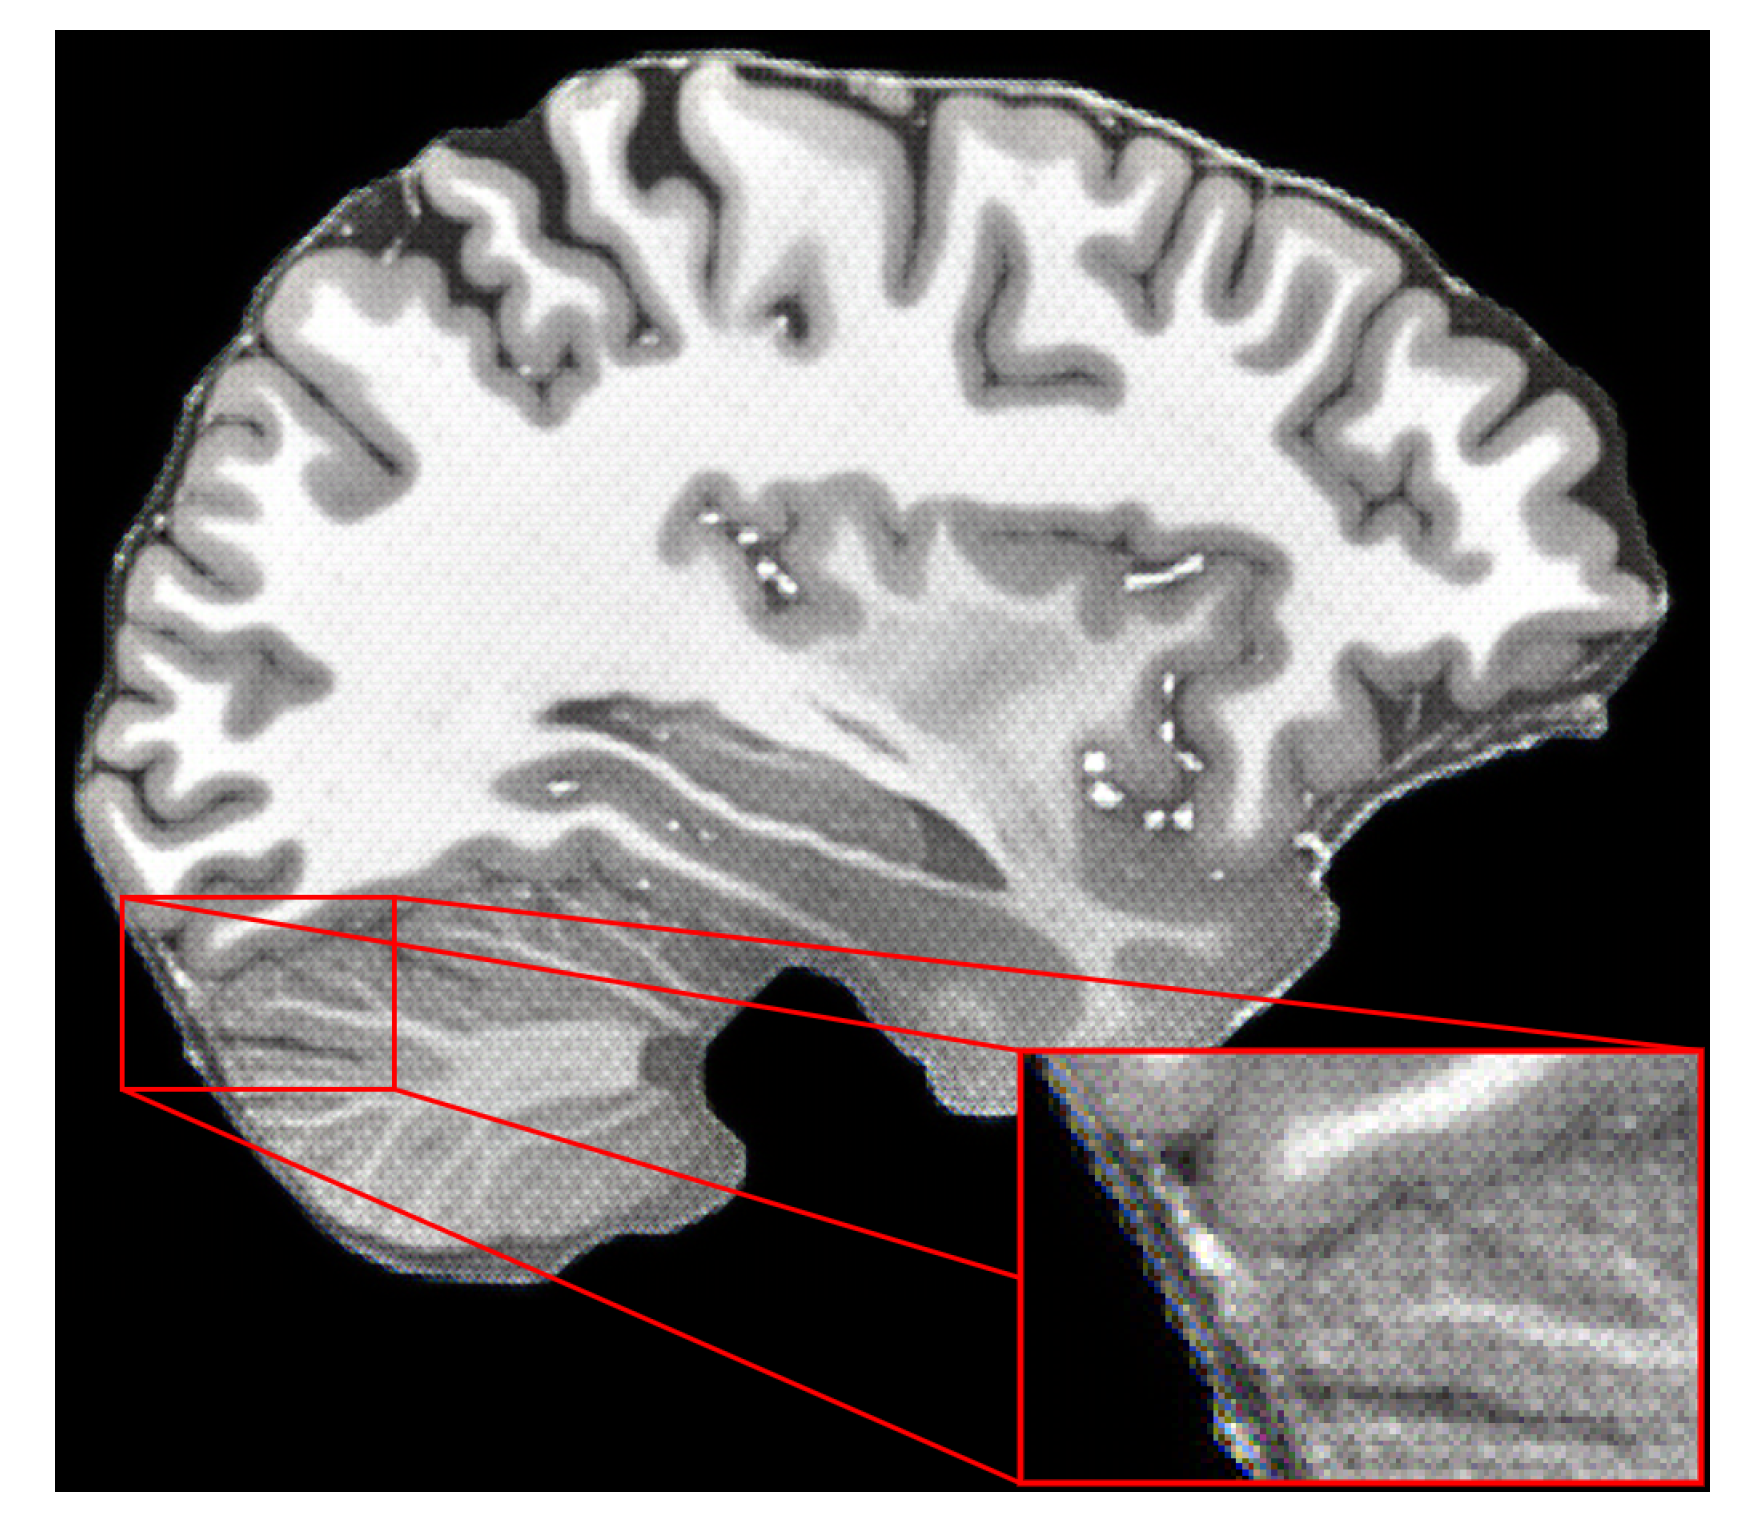

4.3. Results

4.4. Discussion